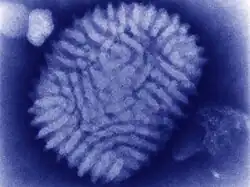

| Myxoma virus (transmission electron microscope) | |